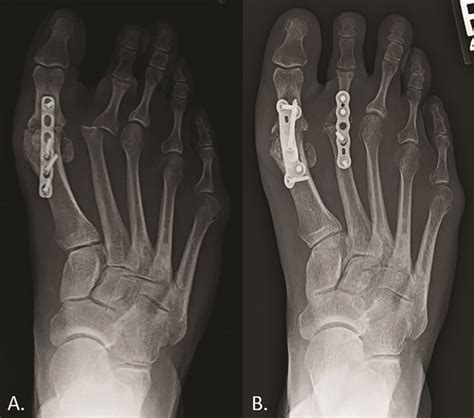

When conservative treatments fail to provide relief, surgical intervention may be necessary. The type of surgery depends on the specific condition and the extent of the damage. Common surgical procedures for 1st MTP joint issues include:

• Cheilectomy: This procedure involves removing bone spurs or other obstructions that limit joint movement.

• Osteotomy: Realigning the bones to correct deformities and improve joint function.

• Arthrodesis: Fusing the joint to eliminate pain and improve stability, although this limits mobility.

• Arthroplasty: Replacing the damaged joint with an artificial implant to restore function and reduce pain.